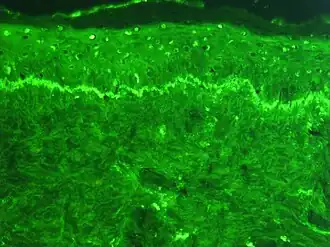

Immunofluorescence is employed in foundational scientific investigations and clinical diagnostic endeavors, showcasing its multifaceted utility across diverse substrates, including tissue sections, cultured cell lines, or individual cells. Its usage includes analysis of the distribution of proteins, glycans, small biological and non-biological molecules, and visualization of structures such as intermediate-sized filaments.[8]

Examination of immunofluorescence specimens can be conducted utilizing various microscope configurations, including the epifluorescence microscope, confocal microscope, and widefield microscope.[12]